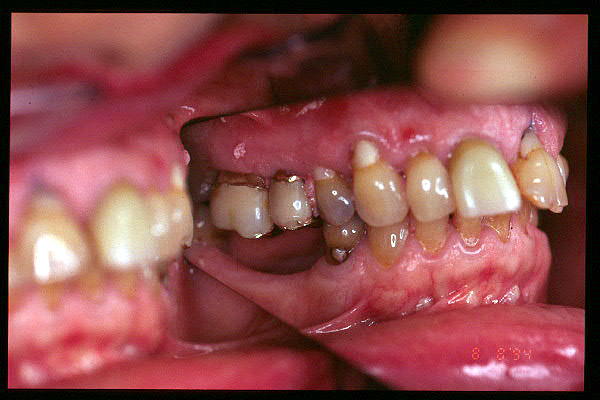

CM Caries, patología periodontal, desgaste.